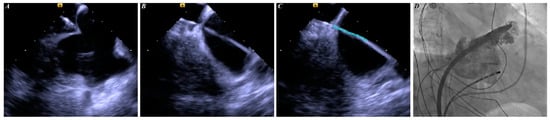

The ICE-guided LAAC was performed as previously described []. The intracardiac images for reconstructing the three-dimensional left atrium model were obtained using a 10-F SoundStar ICE catheter (Biosense Webster). Briefly, the right femoral access was first constructed, and an 11-F sheath for advancing the ICE catheter was inserted into the middle of the right atrium. The catheter was rotated until the atrial septal was fully visible. Finally, the posterior and inferior areas of the fossa ovalis were punctured. The delivery device to the sheath was advanced to the left atrium through the punctured hole. In addition, during the LAAC procedure, the ICE probe was advanced into the left atrium through the same atrial septal puncture hole. The WATCHMAN device (Boston Scientific) was used for the procedure. If the LAA morphology was unsuitable for the WATCHMAN device implantation, the LACbes device (PushMed, Shanghai, China) was instead implanted. Both sheaths have a diameter of 12-F. The diagrammatic flow of these steps is shown in Figure 2.

Figure 2.

Steps of ICE-guided TP procedure. Panel (A) shows ICE image of tenting sign. Panel (B) shows ICE image of SL1 sheath positioned in the left atrium. Panel (C) shows delivered guide wire (green line) into the left atrium along the SL1 sheath. Panel (D) shows that SL1 sheath and guide wire were replaced, and device delivery sheath and ICE catheter were positioned in the left atrium through the same puncture hole. ICE = intracardiac echocardiography; TP = transseptal puncture.